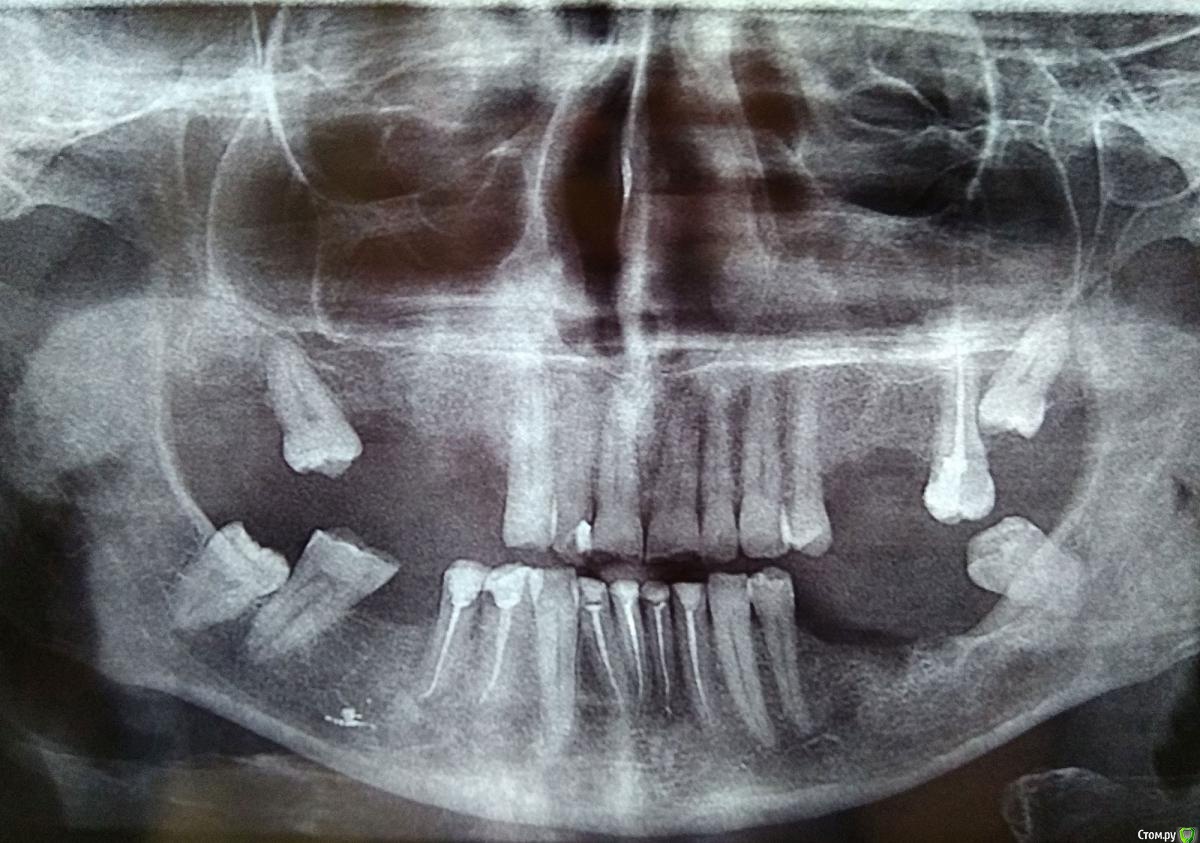

Jonatan Опубликовано 23 октября, 2016 Автор Поделиться Опубликовано 23 октября, 2016 (изменено) Одно и то же снято через стекло и просто на белом листе.Оказывается, послесанационный снимок был (ошиблась). Спасибо. Изменено 23 октября, 2016 пользователем Jonatan Ссылка на комментарий